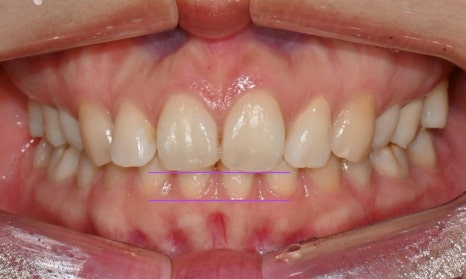

과개교합 치료 전후 사진 비교

총 3달 정도의 치료기간 동안 오른쪽 틀어진 앞니가 가지런하게 배열되었고 치아사이 공간도 타이트하게 닫을 수 있었습니다. 또한 위아래 앞니가 서로 세게 닿지 않도록 위 앞니를 위로 살짝 올려주어 과개교합을 개선하였습니다.